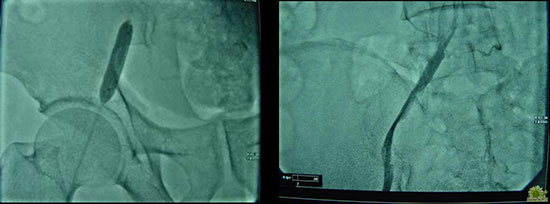

腘静脉穿刺置管

10.jpg

溶栓后静脉完全再通

11.jpg